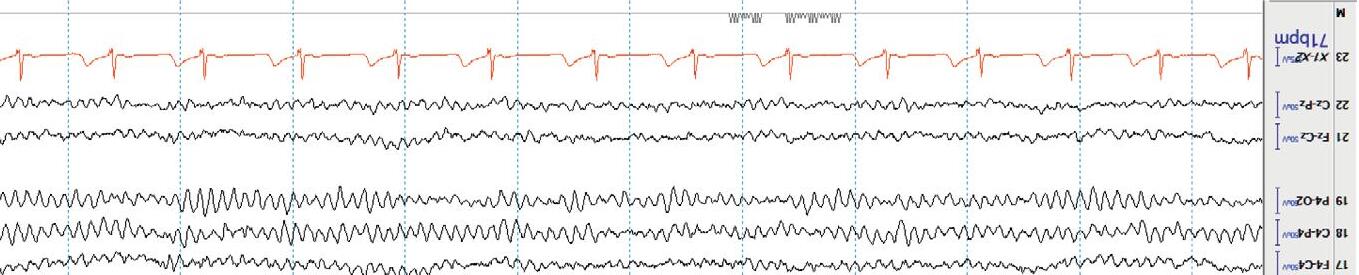

StageN3or slowwavesleep ischaracterizedbyhighamplitude,generalized,semirhythmicdeltaslowing[ 4].Rapideyemovement(REM)sleepis seldomseenintheICU. Figure1.8(b) showsstageN3orslowwavesleep.

Figure1.8(b) NormalstageN3sleep(slowwavesleep).